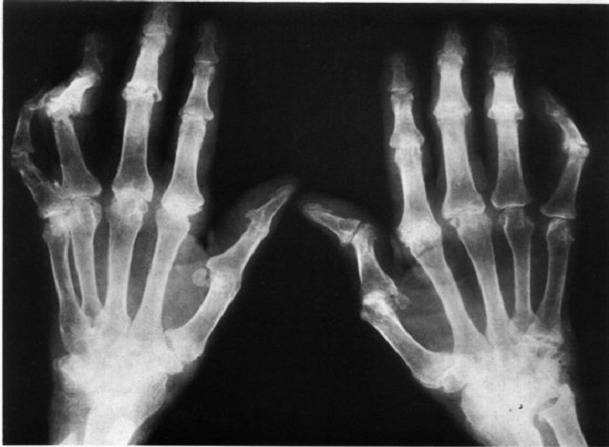

成都风湿医院风湿免疫科陈建春主任指出,类风湿是一种常见的风湿免疫性疾病,以侵蚀性关节炎为主要表现,是一种会致残的疾病,类风湿主要的特点是关节炎症状很难自愈,导致关节周围组织的破坏,出现关节肿胀、疼痛、僵硬以及活动灵活性受限,如果不合理治疗,可能导致永久性关节畸形,较后残废。

类风湿早期有关节红肿热痛和功能障碍,晚期关节可出现不同程度的僵硬畸形,并伴有骨和骨骼肌的萎缩,极易致残。从病理改变的角度来看,类风湿是一种主要累及关节滑膜(以后可波及到关节软骨、骨组织、关节韧带和肌键),其次为浆膜、心、肺及眼等结缔组织的广泛性炎症性疾病。类风湿的全身性表现除关节病变外,还有发热、疲乏无力、皮下结节、胸膜炎、动脉炎、周围神经病变等。广义的类风湿除关节部位的炎症病变外,还包括全身的广泛性病变。